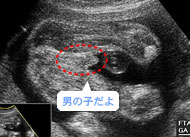

真ん中の突起が、男の子のペニスです。(妊娠23週)